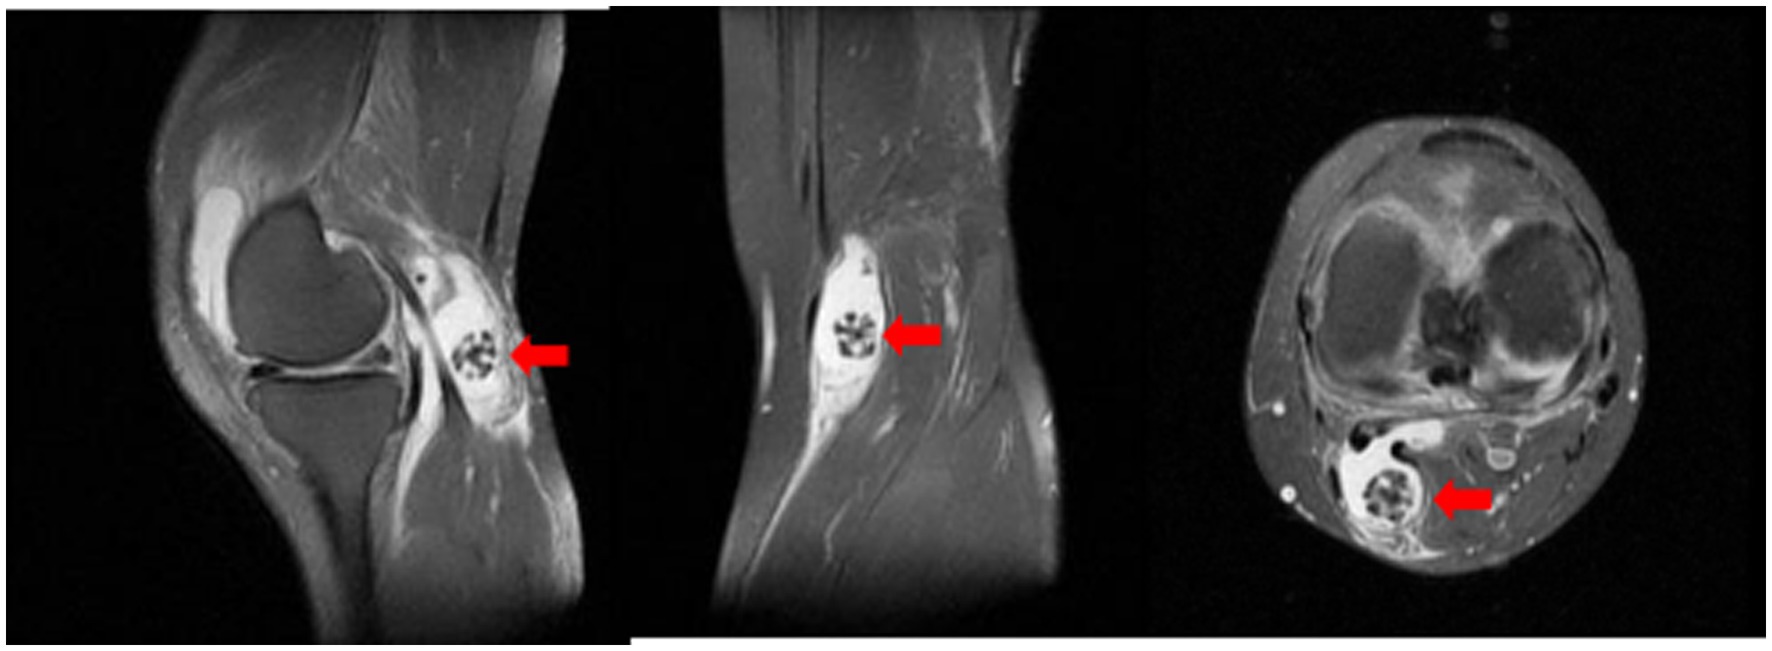

MRI examination revealed the presence of a synovial cyst in the popliteal fossa, accompanied by joint effusion and an intracystic mass exhibiting a spherical coral-like morphology. The synovial cyst was found to communicate with the joint cavity, and significant fluid accumulation was noted in the suprapatellar bursa. Additionally, tears were identified in the anterior and posterior horns of both the medial and lateral menisci. Subchondral bone marrow edema and cystic changes were observed beneath the articular surfaces of the distal femur and the posterior margin of the patella, with damage also noted in the articular cartilage surfaces (Figure 4).

Figure 4. Sagittal T2-weighted MRI of the knee. The red arrow points to the spherical coral-like synovial chondroma within the popliteal cyst (hyperintense fluid signal). Associated joint effusion and degenerative changes are visible.

Popliteal cyst, also known as Baker’s cyst, was first described by Baker in 1877. This cyst typically occurs in the bursa between the gastrocnemius and semimembranosus muscles, situated between the medial femoral condyle, the semimembranosus tendon, and the medial head of the gastrocnemius. Studies have shown that the cyst wall is composed of synovial tissue and usually communicates with the knee joint cavity. Chronic irritation of the knee joint, meniscal injury, or proliferative arthritis can lead to chronic synovial effusion, resulting in the enlargement and distension of the gastrocnemius and semimembranosus bursae. Clinically, it presents as a palpable mass behind the knee joint. In this study, MRI examination of the patient confirmed the presence of knee joint effusion communicating with the popliteal cyst, accompanied by meniscal and articular cartilage injuries.

X-ray is a commonly used imaging method for diagnosing synovial chondromatosis. In lateral knee X-rays, notable calcification or ossified loose bodies can be observed, which is particularly important for diagnosing patients in Milgram stage III. In this study, the patient’s X-ray images exhibited calcified nodules resembling spherical coral. However, X-ray examinations have difficulty distinguishing synovial chondromatosis from other soft tissue tumors, and there is also uncertainty in diagnosing popliteal cysts. Therefore, further CT and MRI examinations are necessary. CT, through three-dimensional reconstruction, can clearly display the number, location, size, and morphological characteristics of loose bodies. For joint effusion and early knee joint lesions, MRI, with its superior soft tissue signal resolution, can effectively illustrate the degree of synovial hyperplasia, the size of popliteal cysts, and the morphology of intra-capsular loose bodies. These imaging findings provide precise data for determining the number and positional relationships of tumors, offering critical references for the complete intraoperative removal of lesions and reducing the postoperative recurrence rate (15).